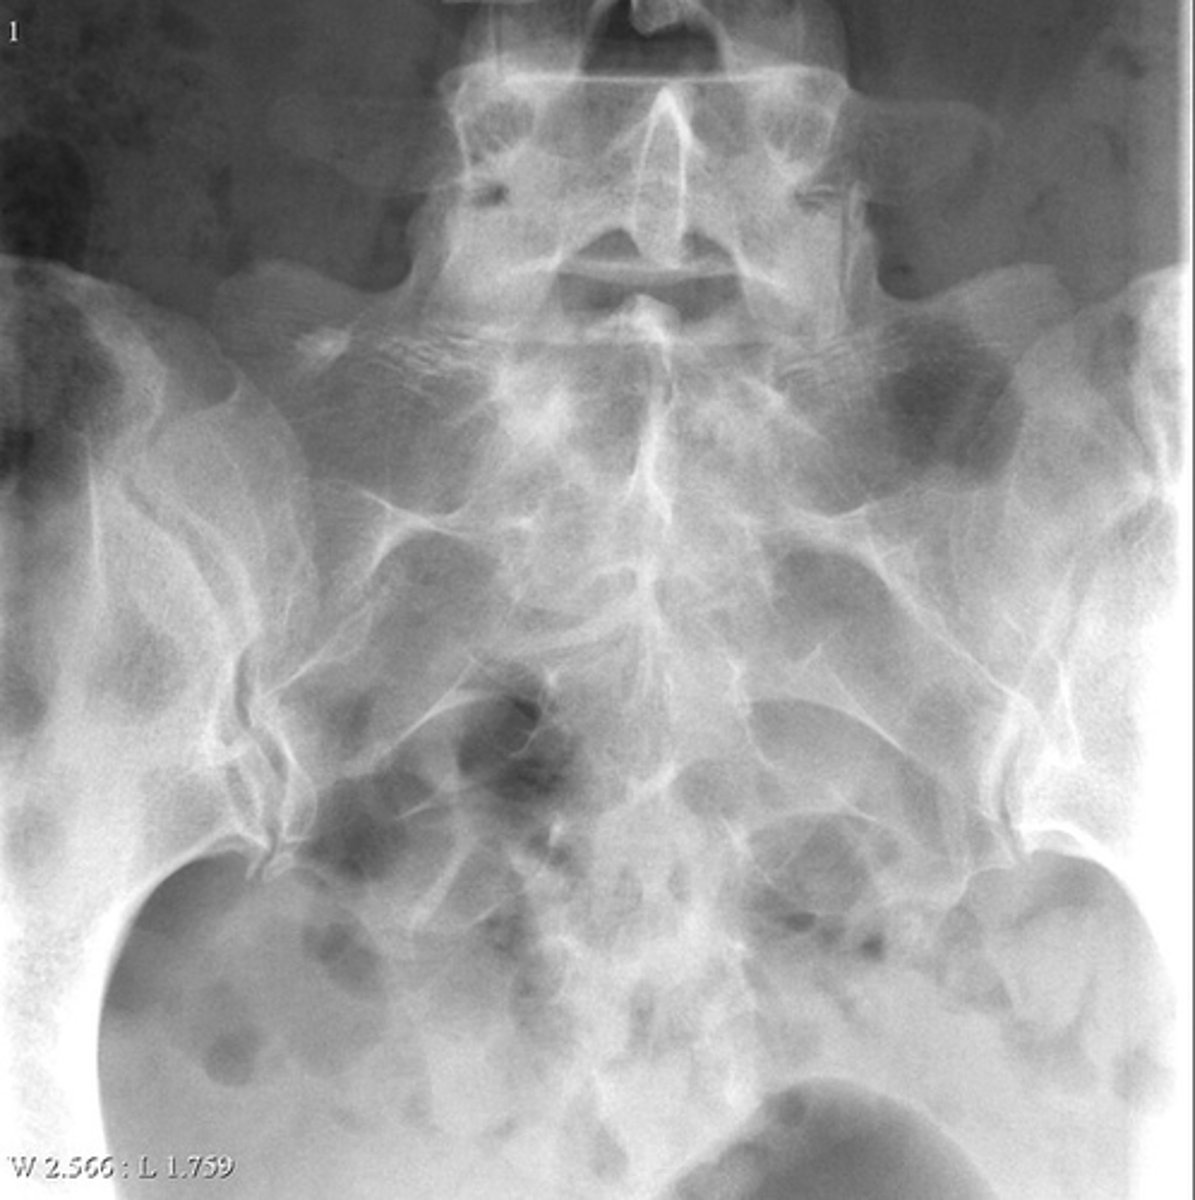

Lateral proximal tibia

Bone

<p>Bone</p>

- Longitudinal: epiphysis/metaphysis (up to joint surface)

- Eccentricity: eccentric

- Transverse: medullary

Location

<p>Location</p>

Monostotic

Mono/polyostotic

<p>Mono/polyostotic</p>

New cards

>1 cm

Size

<p>Size</p>

- Lytic

- Geographic

- Short zone of transition

Behavior

<p>Behavior</p>

Cortex

<p>Cortex</p>

Giant cell tumor

Most likely diagnosis?

<p>Most likely diagnosis?</p>

Refer to orthopedist or oncologist

Next step?

<p>Next step?</p>

Could be aggressive (20%)

Concerns/complications?

<p>Concerns/complications?</p>